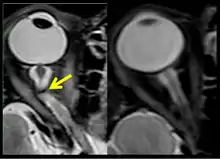

Figure 10: MRI (R+30 days) of the fourth case of visual changes from long-duration spaceflight. There is prominence of central T2-hyperintensity of the optic nerves bilaterally, right greater than left approximately 10 to 12 mm posterior to the globe (arrow) that represents an element of optic nerve congestion.

Figure 11: MRI (R+30 days) of the fourth case of visual changes from long-duration spaceflight. Tortuous optic nerve and kink on left (arrow). Control orbit on the right.